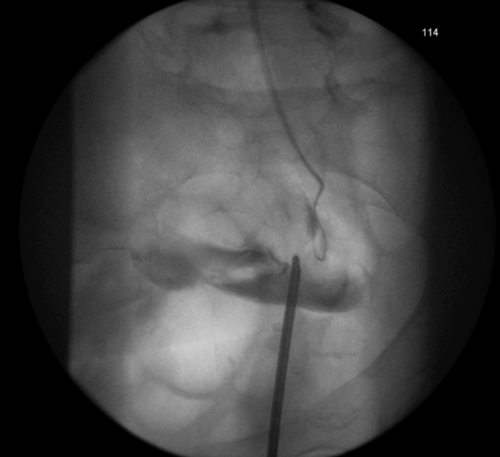

Figure 1: An example of the rendezvous procedure for an iatrogenic injury to

distal ureter during a laparoscopic pan-proctocolectomy for ulcerative colitis.